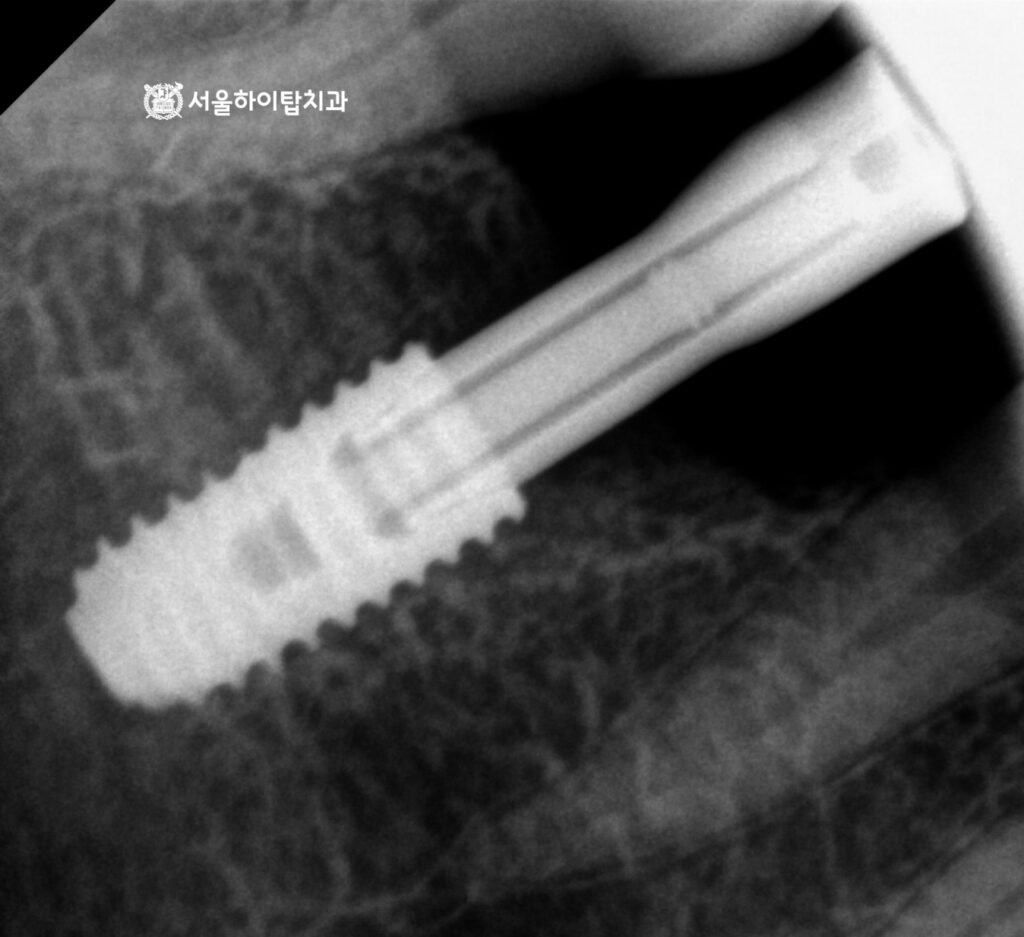

임플란트 식립 완료 – 골 유착

만수동 치과 에서는 앞선 가상 식립 시뮬레이션을 바탕으로

계획한 위치와 각도에 맞게 픽스처가 안정적으로 식립된 것을 확인할 수 있습니다.

주변 치조골과의 관계, 식립 깊이, 방향 모두

사전에 설정한 계획 범위 내에서 정확하게 이루어졌습니다.

이후 일정 기간 동안 픽스처와 주변 치조골이

단단하게 결합되는 골유착 과정을 충분히 거치게 됩니다.